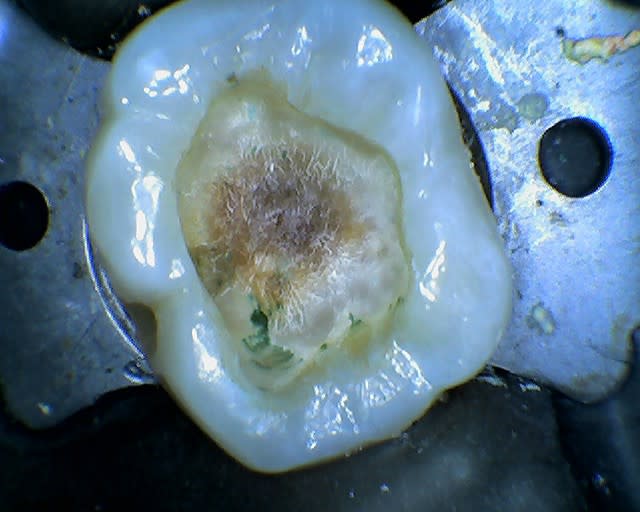

le curetage me paraissait ok et voila ce que j’obtiens...

Image radiotransparente est due peut être, bêtement, aux effets indésirables de ce type de matériau (contraintes + stress de polymérisation) .

- Est-ce une simple rétraction du matériau résineux?

Quel résultat lors du séchage de la cavité. Dentine séchée ou asséchée, dentine humide, dentine « mouillée » car : « un excès d’eau signifie la formation de lacunes au sein de l’interface ». Notons que les notions de séchage, d' humide, de légèrement mouillée est cliniquement difficile à apprécier car non quantifiable

Quelle méthodologie a été employée lors de l'insertion du composite : en un seul bloc ou stratification? D'où, quelle épaisseur du composite ?

Si stratification : horizontale ou oblique? Car : « la stratification oblique est assez difficile à réaliser, surtout dans la zone proximale lorsque celle-ci est étroite et profonde »

Puissance utilisée de la lampe à polymériser? La course au gain de temps nous amène à utiliser la puissance maximale de la lampe lorsque celle-ci dispose d'un variateur, mais est-ce raisonnable?

En définitive, toutes les interrogations citées ci-dessus font que le composite est un matériau de restauration qui s’accompagne le plus souvent d’un cortège de résultats imprévisibles pour ne pas dire indésirables. Donc :

Pourquoi une obturation OM au composite foulée sur une 16 sachant les risques de ce matériau ?